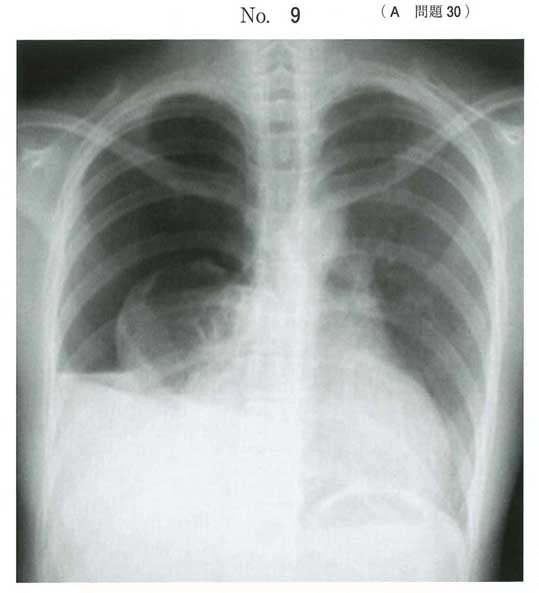

血気胸

109D31の年齢設定が18→20になっただけで文言、検査値、X線の画像まで全部同じ。

血気鏡→ドレナージは安直ですね。出血コントロール不良が強調されていて、問題文最後にバイタルまで書いてくれていることも作問委員からのヒントに思えます。

記述から外傷かは判別できませんが、明らかに外傷を想定した問題と思われます。血気胸でイニシャル1000ml排液あれば即開胸です。なぜ、2時間待ったのでしょうか?外傷学会ならめちゃくちゃ叩かれますよ。